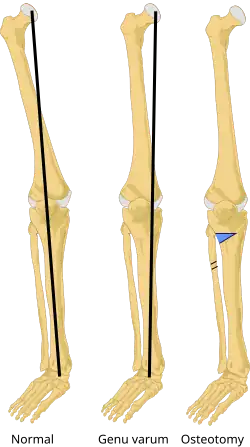

Genu varum (also called bow-leggedness, bandiness, bandy-leg, and tibia vara) is a varus deformity marked by (outward) bowing at the knee, which means that the lower leg is angled inward (medially) in relation to the thigh's axis, giving the limb overall the appearance of an archer's bow. Usually medial angulation of both lower limb bones (fibula and tibia) is involved.[1]

On projectional radiography, the degree of varus or valgus deformity can be quantified by the hip-knee-ankle angle,[9] which is an angle between the femoral mechanical axis and the center of the ankle joint.[10] It is normally between 1.0° and 1.5° of varus in adults.[11] Normal ranges are different in children.[12]

Treatment for children with Blount's disease is typically braces but surgery may also be necessary. In children guided growth surgery is used to gradually correct/straighten the bow legs.[13] For teenagers osteotomy or bone cutting is often used to correct the bone deformity. The operation consists of removing a piece of tibia, breaking the fibula and straightening out the bone; there is also a choice of elongating the legs. If not treated early enough, the condition worsens quickly.[14]